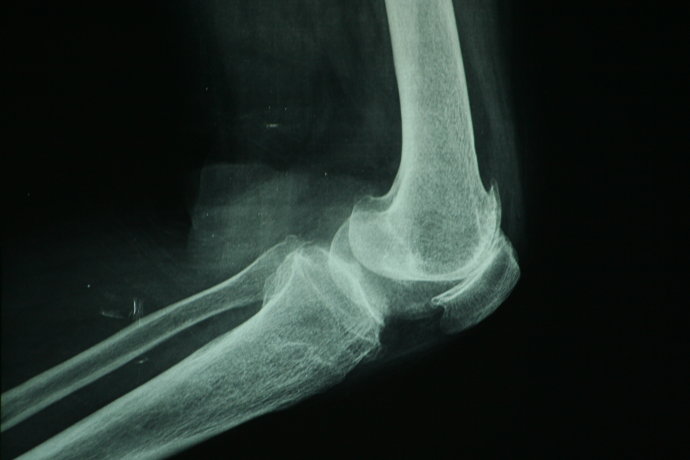

退行性膝关节炎辅助检查

X片检查